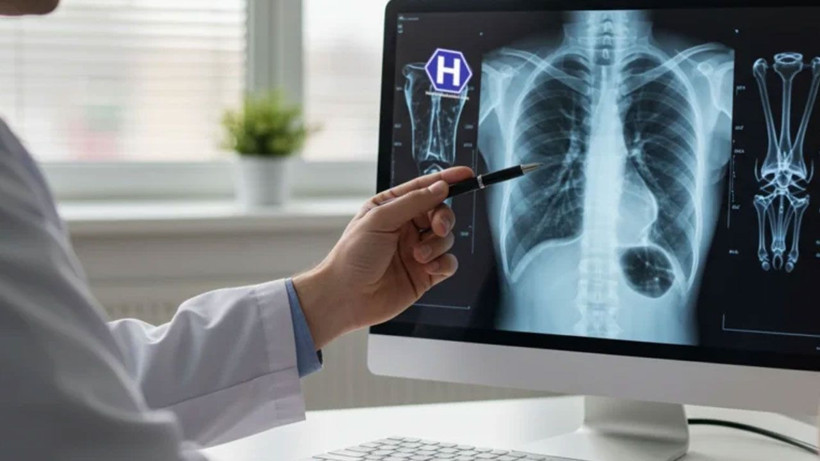

Türkiye'de her yıl 45 bin yeni vaka! Bu illere dikkat: Risk daha fazla! - Resim: 4

"Bilimsel çalışmalar, özellikle PM2,5 düzeyinde metreküpte her 10 mikrogram artışın, akciğer kanseri riskini yüzde 15 ila 22 yükselttiğini gösteriyor. Bu partiküller çoğunlukla trafik egzozu, sanayi emisyonları, kömür ve biyokütle yakımı gibi kaynaklardan ortaya çıkıyor. Boyutları çok küçük olduğu için vücudun doğal filtreleme mekanizmalarını kolayca aşabiliyor ve uzun süre akciğer dokusunda birikerek zarar verebiliyorlar."